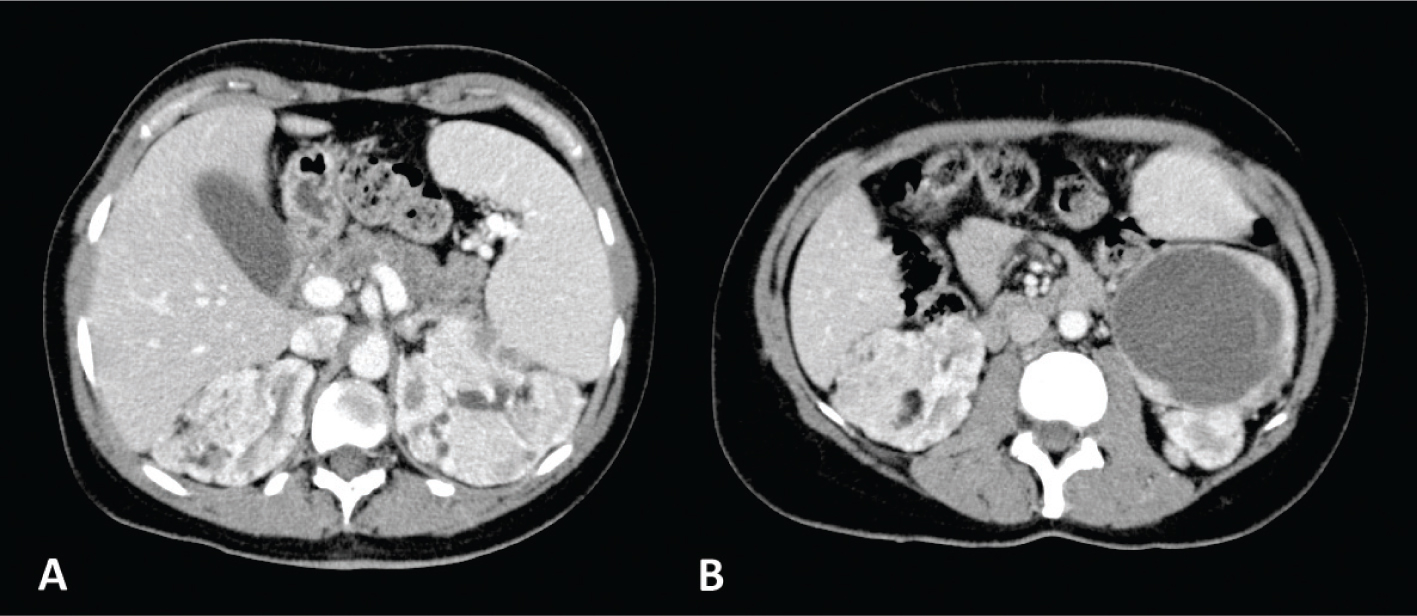

Fig 3

Figure 3. Unenhanced CT axial scan of the abdomen (A and C) and CT of the abdomen during arterious phase (B and D) of a 53-year-old woman showing the presence of classic AMLs, recognizable by the adipose component of the lesion.